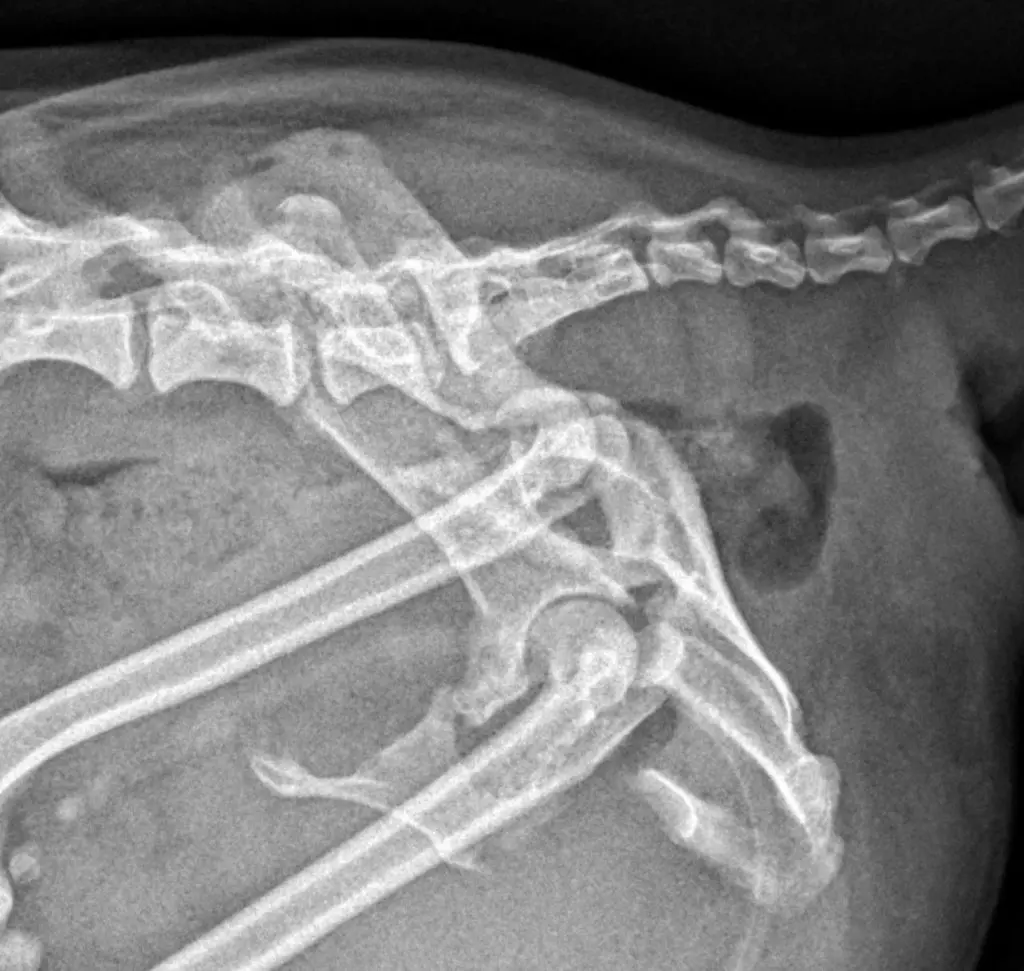

En primer lugar realizamos un completo examen ortopédico, en el que observamos una paraparesia no ambulatoria con incapacidad de mantener peso en la estación. A la palpación de la pelvis se puso de manifiesto dolor muy marcado, asociado a crepitación y una dismetría pélvica considerable.

Para obtener un diagnóstico definido, procedimos a realizar un protocolo diagnóstico completo, que incluyó un estudio radiológico y tomográfico de la pelvis. Gracias a las imágenes pudimos confirmar el diagnóstico, una fractura múltiple de pelvis con luxación sacroiliaca derecha, y luxación coxofemoral izquierda a consecuencia de una fractura conminuta del acetábulo.

Para poder definir con mas precisión todos los daños y establecer el mejor plan quirúrgico realizamos una tomografía computarizada (TAC) de la pelvis.